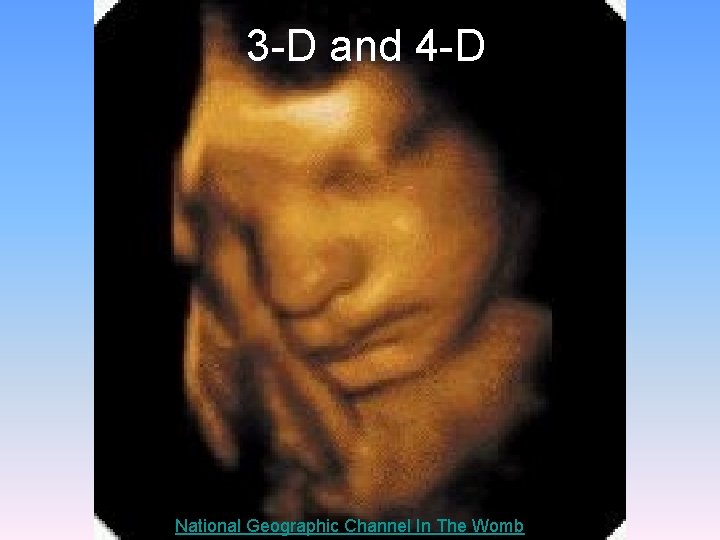

2 -D

3 -D and 4 -D National Geographic Channel In The Womb